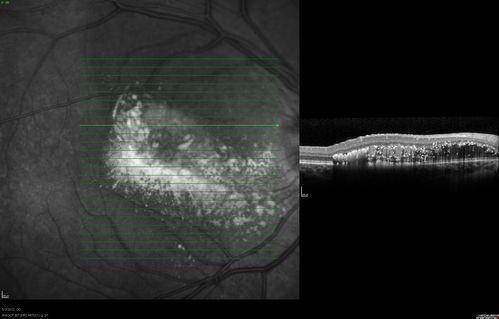

oct superior macula 1. od

Coats disease

saunders/pavan/usf eye institute